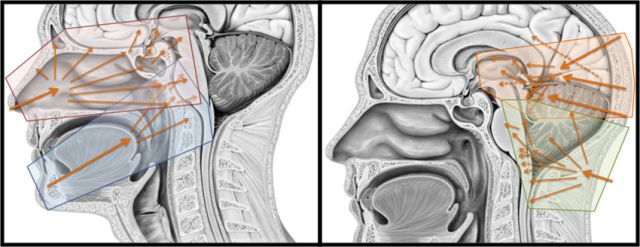

手术体位及入路

手术体位个性化选择